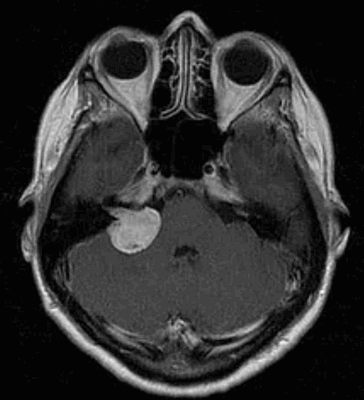

Учитывая что у всех пациенток было прогрессирующее снижение слуха, гипорефлексия лабиринта при отсутствии указаний на перенесенный гнойный отит, вестибулярный нейронит и болезнь Меньера в анамнезе, мы заподозрили невриному VIII пары черепно-мозговых нервов (ЧМН), несмотря на отсутствие изменений по данным многочисленных МРТ, КТ головного мозга и рентгенографии височных костей по Стенверсу. Пациентам произведено МРТ головного мозга с введением контрастного вещества (омнискан или магневист), в результате диагноз акустической шваноммы был подтвержден. В двух случаях (больная Ш., больная К.) новообразование локализовалось в проекции мостомозжечкого угла с деформацией прилежащих структур, размером до 29×25×27 мм, с распространением по ходу VII и VIII пар ЧМН, практически на всю длину внутреннего слухового прохода (до 15 мм), в одном случае (больная А.) — во внутреннем слуховом проходе, размером 10×16×6 мм.

На Т2-взвешенных МРТ головного мозга невриномы имеют округлую или овальную форму, изоинтенсивны или слегка гиперинтенсивнее белого вещества, хорошо видны на фоне яркого ликвора цистерны. Крупные опухоли могут подвергаться кистозной дегенерации и включать сосуды. Мелкие невриномы имеют компонент во внутреннем слуховом проходе и как бы “утолщают“ нерв на МРТ изображениях. Как показывает опыт МРТ СПб полностью внутриканальцевые невриномы встречаются редко. МРТ в СПб при шванномах мы проводим обычно с контрастированием. Контрастирование неврином при МРТ с контрастированием хорошее, обычно однородное. Нельзя забывать, что во внутреннем слуховом проходе также может быть воспалительный процесс (неврит), приводящий к сходной клинической симптоматике. При МРТ неврит виден как отёк нерва, имеется контрастное усиление на МР томограммах.

МРТ головного мозга. Невринома слухового нерва слева с внутриканальцевым компонентом. Аксиальные Т1-зависимая МРТ, Т1-зависимая МРТ с контрастированием, и корональная Т1-зависимая МРТ с контрастированием.

Невринома слухового нерва в цистерне и внутреннем слуховом проходе. Киста (чёрная стрелка). Аксиальная Т1-взвешенная МРТ, неоднородное контрастирование.